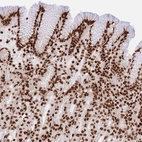

Immunohistochemical staining of human stomach shows strong nuclear positivity in glandular cells.